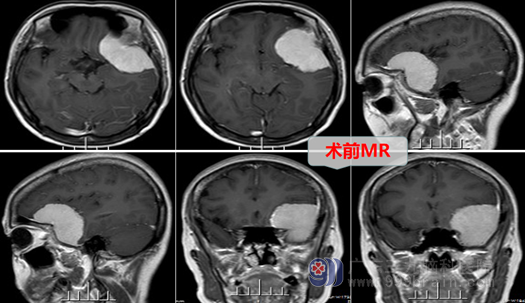

邱阿姨顺利的入住到三九脑科医院外十科,主治医师是邓心情医生,经过详细询问病史,专科的检查,结合患者的症状、体征,明确诊断为:左侧蝶骨嵴脑膜瘤,这是一个血供丰富、切除难度较大的良性肿瘤。外十科团队在欧阳主任带领下,最后制定完整的治疗方案,在征得邱阿姨及家属的同意后,择期行“左侧蝶骨嵴脑膜瘤切除术”,手术进行得顺利,肿瘤被完全切除,出血量很少,神经功能被良好保护。术后邱阿姨恢复很好,她高兴地说道:”感谢你们为我解决了这6年多的头痛,哎…这头痛还真的不能忽视,我以为平日偶尔头痛一下不是个问题,没想到脑袋还长瘤子了,幸好遇到优秀的医生、护士团队,感谢你们给我一次重生的机会!”